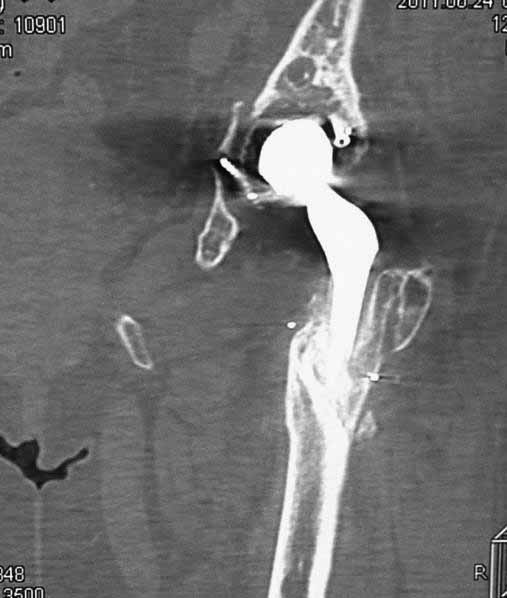

Уважаемые коллеги. Хотелось бы услышать мнения и советы по представляемому случаю. Пациентка 45 лет. Бесцементное эндопротезирование левого тазобедренного сустава 6 лет назад (впадина RM, Mathys, металл-металл, ножка Зульцеровская). За 10 лет до протезирования – коррегирующая остеотомия бедренной кости, которая не срослась в течение года до удаления пластины, а затем срослась в течение 3 месяцев иммобилизации в кокситной повязке. После протезирования получилось наблюдать пациентку почти постоянно, поскольку через 2 года синтезировал ей лодыжки на оперированной стороне, затем, через несколько месяцев удалил фиксаторы, а в 2009г. резецировал мениск на противоположной стороне. Боли все эти годы не беспокоили. Пациентка чуть выше среднего роста, вес тела нормальный. Физические нагрузки переносила хорошо. Работает на 7 этаже без лифта. Год назад экстирпация матки по поводу лейомиомы больших размеров. Несколько месяцев назад появились боли в области левого тазобедренного сустава. При рентгеновском и КТ исследованиях (июль с.г.) – нестабильность тазового компонента. От предложенной замены протеза пациентка на тот момент, слава богу, отказалась. Через какое то время боли в области левого тазобедренного сустава практически полностью прошли, а около 2 месяцев назад появилось ощущение патологической подвижности таза и боли в паху справа, которые через некоторое время уменьшились, а потом снова усилились после значительных физических нагрузок (много ходила по песку на пляже, носила тяжести). Ежедневно принимала диклофенак. На рентгенограммах – переломы правой лонной кости. Сейчас госпитализирована из-за болей в паху справа. Боли слева не беспокоят. На фоне снижения нагрузок в стационаре боли значимо уменьшились. Способна ходить без средств дополнительной опоры.В анализах крови чуть повышены трансаминазы и гамма-ГТ, моча без особенностей.

Вопросы: -правильно ли я расцениваю переломы как стрессовые на фоне неполноценного таза (pelvic insufficiency stress fractures)? -Можно ли так же расценить ситуацию на стороне протеза и, соответственно, не торопиться с ревизией, рассчитывая на вторичную стабилизацию? Уж больно не хочется менять ножку. -Если думать о ревизии, то когда? На представленных снимках тазобедренный сустав до и сразу после операции, затем 2 снимка 2009г., когда ничего не беспокоило, затем КТ 2-х месячной давности и вчерашние рентгенограммы обоих тазобедренных суставов.

Сергей, очень возможно, что перелом и стрессовый, но мне видится, что его причина в нестабильности чашки. Дело в том, что в отличии от ножек, чашка при своей дестабилизации болит гораздо меньше и больные терпят до последнего.

При сравнении рентгенограмм можно увидеть насколько чашка переместилась от места своего первичного расположения. От опрокидывания ее удерживают конструкционные элементы "рожки". Без них ситуация, возможно, уже была бы катастрофической (чашка в тазу). Думаю надежды на вторичную интеграцию, могут быть обмануты и ревизии не избежать.

Если говорить о ревизии, то просто не будет и вероятность установки реконструктивного кольца достаточно высока, однако можно попробовать установить бесцементную высокопористую (для вторичной стабилизации врастанием) чашку с винтами , а по ходу операции решить вопрос о необходимости стабилизации таза пластиной.

Вопрос о замене ножки зависит от ее стабильности и длины конечности. Если уже сейчас нога длиннее или после вмешательства центр ротации низведется - придется ногу менять.